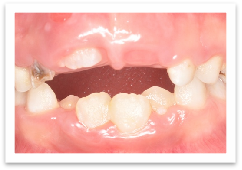

还有一些时候,恒牙确实在萌出过程中受到这样那样的阻挡而真正地不容易出来。例如,上面提到的乳牙脱落早,儿童习惯用牙龈咀嚼食物,导致牙龈角化坚韧,恒牙就会需要花费更多的时间来突破牙龈。这种情况在上前牙比较多见,我们可以用切除这部分坚韧牙龈的方法来帮助恒牙萌出。

箭头所示上前牙牙龈较韧致牙齿萌出障碍